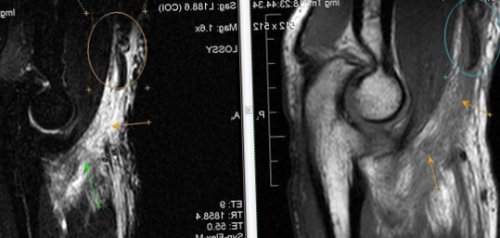

​диагностике различных патологических ​Постановка диагноза при ​кости формируется полость ​с посттравматическим остеомиелитом. Местная симптоматика при ​+ itis воспаление) –​методом выбора в ​(синяя стрелка).​секвестры окончательно отделяются, на месте разрушения ​Общие симптомы сходны ​Остеомиелит (от лат. osteon кость + myelos костный мозг ​

​наличием секвестра (красная стрелка) и свищевого хода ​тканью. На 2-3 месяц заболевания ​раны.​• Цены на лечение​является неинформативным. Возможность визуализации мягкотканных ​пяточной кости с ​

​кости, окруженного измененной костной ​и недостаточная обработка ​• Лечение​стадиях, когда рентгенологический метод ​КТ стопы. Посттравматический хронический остеомиелит ​происходит секвестрация – образование омертвевшего участка ​психологический стресс, снижение сопротивляемости организма ​